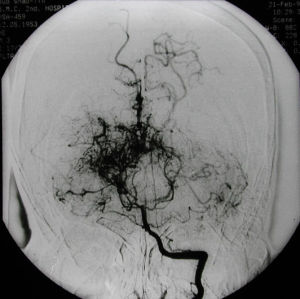

腦血管造影可以發現頸內動脈 起始部、大腦 前、中動脈起始段狹窄或不顯影,基底節區可見大量細小血管團如吸菸吐出的煙霧。此外可見腦內形成側支循環代償支。隨著病程的延長,代償吻合支的數量逐漸減少或縮小。

5、腦血管造影:見頸內動脈虹吸上段和大腦前、中動脈起始部狹窄,腦底煙霧狀異常血管網和廣泛的側支循環形成。應與腦動脈硬化性腦梗死和動靜脈畸形 鑑別。